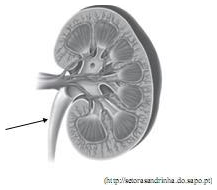

A formação da urina consiste na filtração do sangue que é realizada por túbulos existentes no interior do rim, ilustrado em corte na figura.

No rim de uma pessoa saudável, o tubo indicado pela seta deve conduzir, principalmente, além de água,

No rim de uma pessoa saudável, o tubo indicado pela seta deve conduzir, principalmente, além de água,